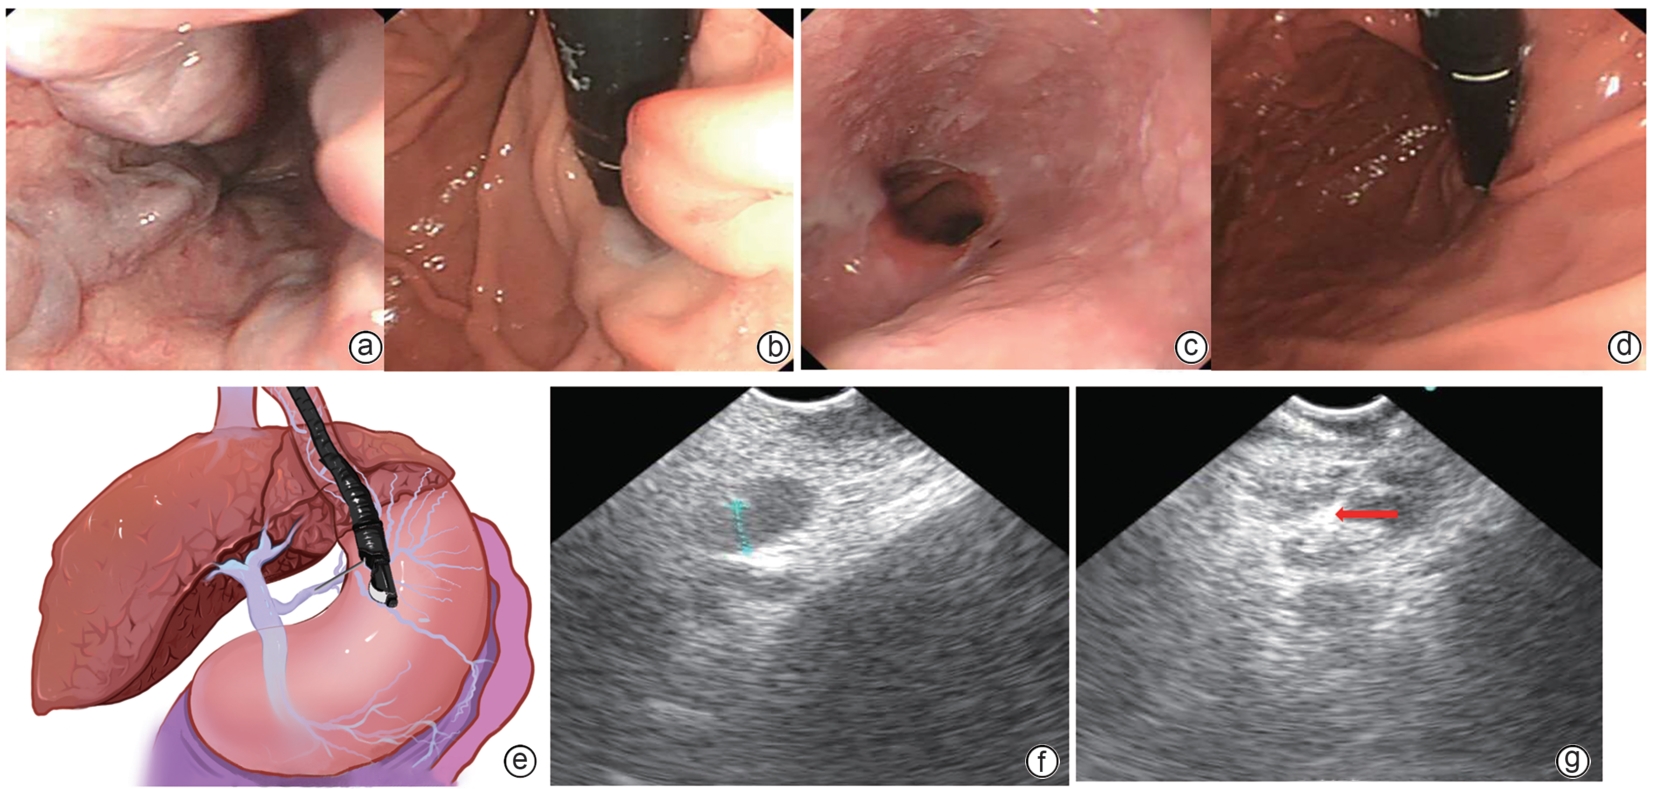

On August 31, 2025, the Asian Pacific Association for the Study of the Liver (APASL) updated and released management of acute variceal bleeding: updated APASL guidelines (2025 edition), which systematically elaborates on the definition, diagnosis, assessment, and treatment of acute variceal bleeding. This article gives an excerpt of the recommendations in this guideline.